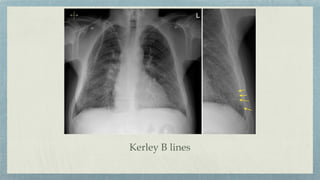

Kerley B lines

Frontal View Lateral